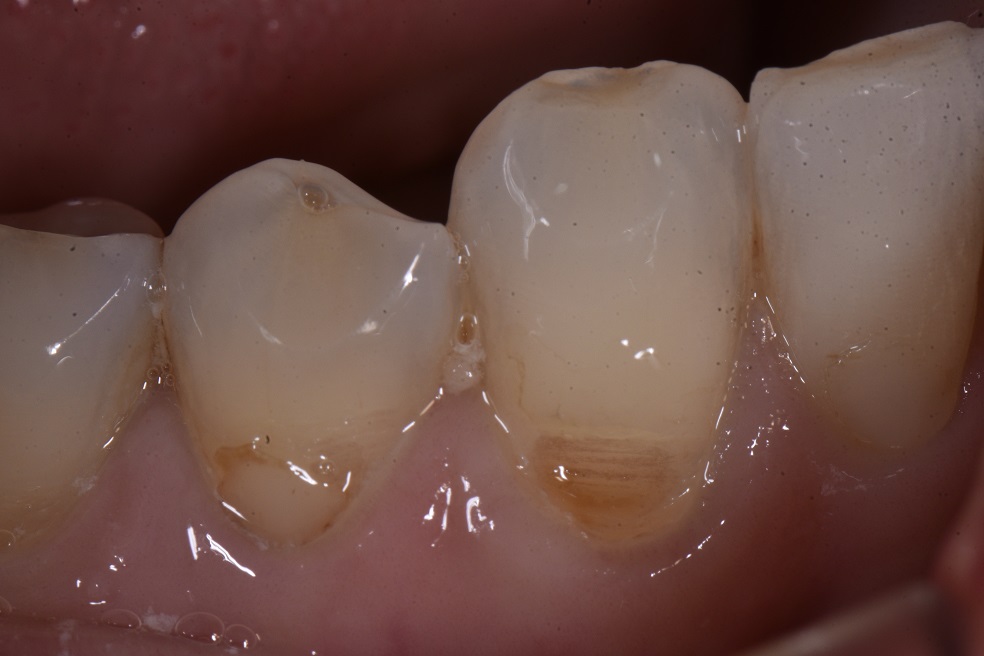

Non-carious cervical lesions or Class V’s are such a breeze with this one material. One material to simply your life and put that smile on your dial. Universal shade = 50:50 ratio of A2:A3.